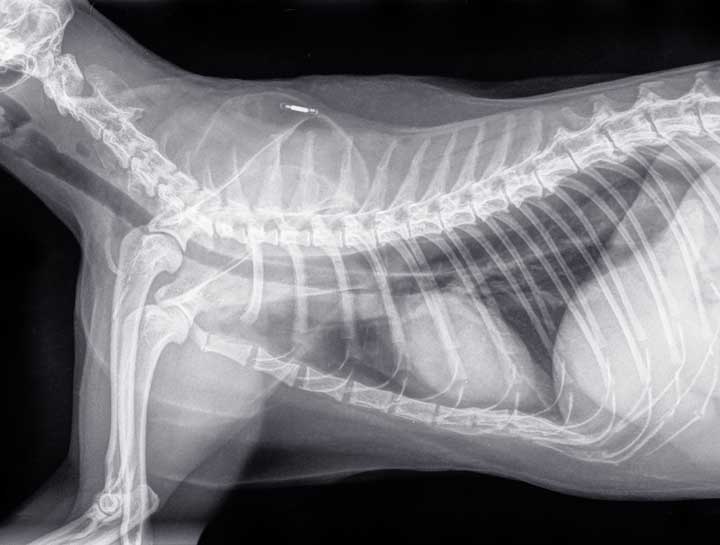

A microchip is an electronic device that’s only about the size of a grain of rice. It gets implanted between the shoulder blades and remains there indefinitely, although it is possible for a microchip to migrate. The implant procedure is relatively painless and it’s as quick and easy as receiving a shot.

Pet microchip on xray